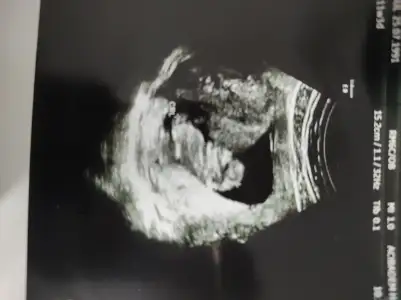

Eki Görüntüle 473829 bu bir erkek bebek genital nub cikintisi gayet yukarda

Eki Görüntüle 473831 simdi burada cikintilara bakin eger bel popo cizgisine paralel ise kiz

yok 30 derecelik bir aciyla yukari bakiyorsa erkek

Eki Görüntüle 473837 bu benim kizim cikinti gayet net ve ortada ve ben kizim diyooo

hani dr lar 12. 13. haftalarda belli degil ama

kemik yapisina gore kiz gibi

yahut erkege benziyor diyorlar ya

iste o nub teorisi kizlar dr buradan yola cikiyor